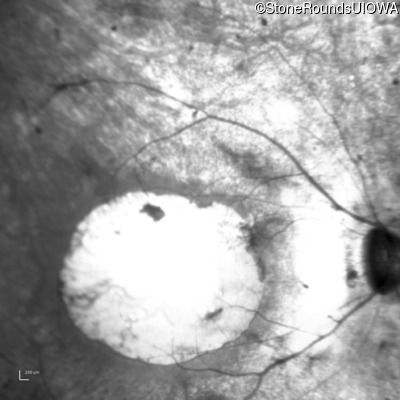

Age at visit: 15 years

OD OS

This 15 year old male had a macular abnormality noted two weeks ago when he was refracted for his first pair of glasses. Bone spicule-like pigmentation was first noticed a year later (age 16) during a routine follow-up eye exam.

Age at visit: 16 years